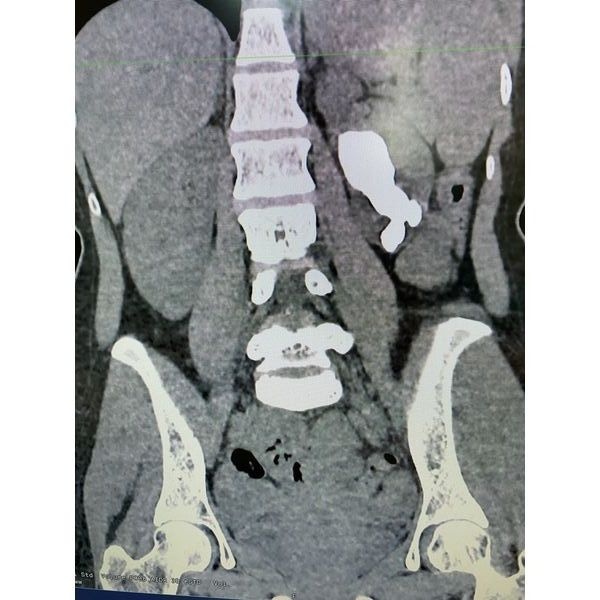

По результатам компьютерной томографии (КТ) почек и мочевыводящих путей с контрастированием:

- обе почки своевременно выделяют контрастное вещество;

- коралловидный камень в лоханке, средних и нижних чашечках левой почки, размер — 22 × 36 × 64 мм, плотность — 1409 НU;

- умеренное расширение полостных элементов левой почки;

- мочеточники не изменены.